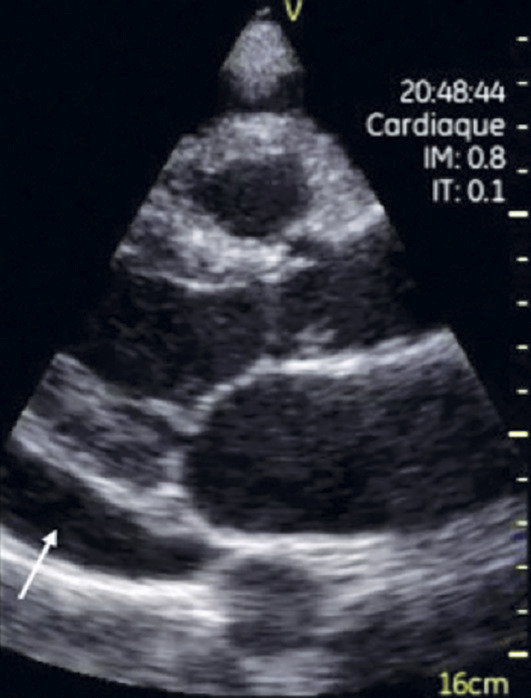

Les ultraportables sont des appareils sans fil fonctionnant sur batterie (autonomie : 1 heure) et pesant moins de 1 kg. Plusieurs sont disponibles avec des spécificités variables, selon le constructeur. L’écran – souvent équivalent à celui d’un smartphone – et la sonde sont de taille réduite (fig. 1).1 Grâce à des applications, mobiles, smartphone ou tablette servent d’écrans, une fois connectés à la sonde de l’échographe. Cependant, actuellement, l’évaluation morphologique et fonctionnelle est partielle. Notamment il n’y a pas de quantification hémodynamique par étude des flux en doppler pulsé, continu et tissulaire. Seule l’analyse bidimensionnelle (2D), le doppler couleur et des modalités de mesures limitées sont possibles avec ce type d’appareil. Les résultats sont bien corrélés à ceux des échographies classiques (notamment FEVG et épanchement péricardique ; fig. 2).

En comparaison avec une échocardiographie classique, différentes structures peuvent être analysées, avec de bonnes sensibilité et spécificité.

Taille et fonction globale du VG. L’interprétation de troubles de la cinétique segmentaire (évoquant une atteinte artérielle coronaire) est cependant plus difficile et requiert une échographie complète faite par un cardiologue sur une machine plus perfectionnée, disposant de toutes les modalités ultrasonores de quantification.

Taille des cavités droites et pression dans l’oreillette droite. Cette dernière via l’analyse du diamètre de la veine cave inférieure (valeur seuil 21 mm) et de sa compliance (< ou > 50 % de variation de calibre entre l’inspiration, dimensions minimales, et l’expiration, dimensions maximales). Une VCI fine (< 21 mm) et compliante (variation > 50 %) est associée une POD à 3 mmHg ; dilatée (> 21 mm) et non compliante (variation < 50 %) : la POD est à 15 mmHg.

Valvulopathies. L’échographie ultra- portable confirmerait les résultats d’une auscultation anormale et aurait aussi un rôle dans le dépistage des vices valvulaires, aboutissant à une sténose ou à une régurgitation. Lorsque l’atteinte des valves dépasse le stade modéré, une échographie plus complète est nécessaire.

Aorte, notamment en cas de suspicion de syndrome aortique aigu (dissection, hématome intramural, ulcère athéromateux pénétrant).

Épanchement péricardique et/ou tamponnade.

Insuffisance cardiaque, en particulier pour guider la démarche diagnostique (fonction ventriculaire gauche, statut volémique).

Patient en soins intensifs (évaluations itératives des fonctions ventriculaires et du statut volémique).